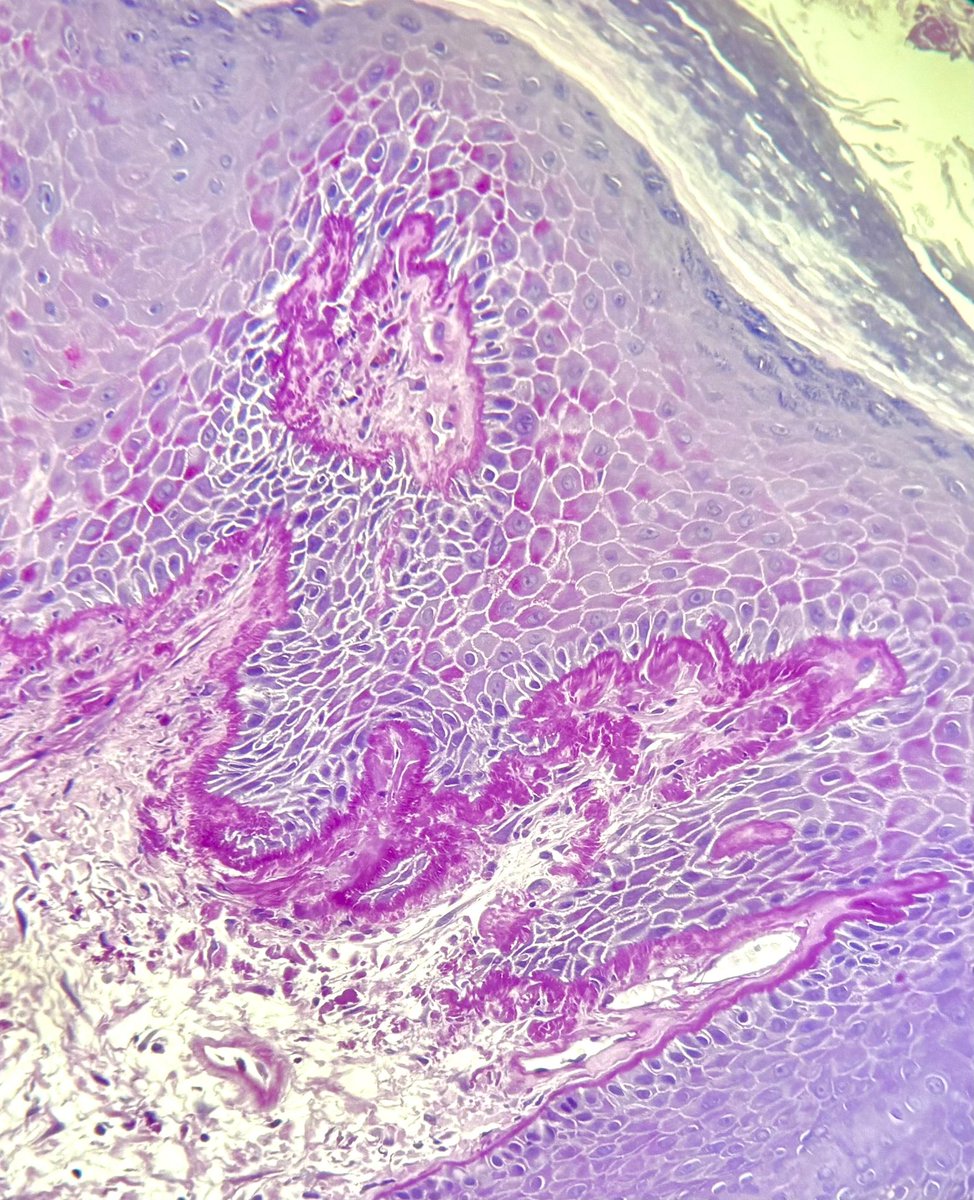

#ClinicalPathologicChallenge 63F with known Darier disease (DD) presented to the ED after 1 week of fevers, gastroenteritis, and rapidly progressive skin blistering and desquamation. P/E: Diffuse epidermal sloughing with hemorrhagic crusting on the vermillion border

63F with known Darier disease (DD) presented to the ED after 1 week of fevers, gastroenteritis, and rapidly progressive skin blistering and desquamation.

P/E: Diffuse epidermal sloughing with hemorrhagic crusting on the vermillion border